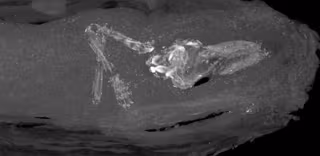

El examen utilizando imágenes de rayos X en el Museo Fitzwilliam fue concluyente, y sugirió que podría contener un pequeño esqueleto. Por lo tanto, se decidió escanear con micro CT (tomografía computarizada) el pequeño bulto en el Departamento de Zoología de la Universidad de Cambridge. Las imágenes de cortes transversales dieron las primeras imágenes de los restos de un pequeño cuerpo humano dentro de los envoltorios, los cuales permanecen inalterados.

El análisis de los dedos de las manos y los pies permitió datar ocn exactitud el periodo de gestación del feto en no más de 18 semanas.